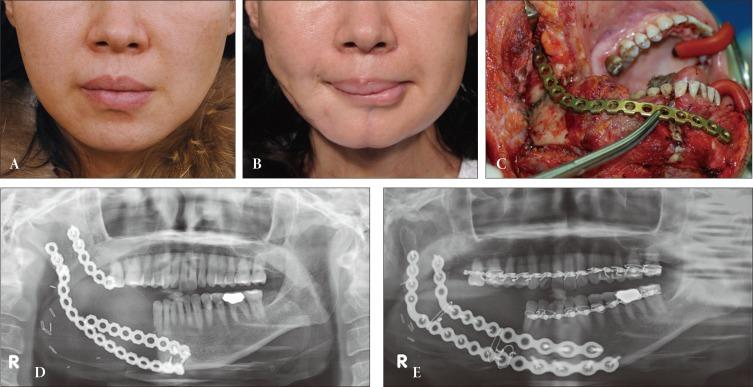

The fibular free flap has been used as the standard methods of segmental mandibular reconstruction. The objective of mandibular reconstruction not only includes restored continuity of the mandible but also the recovery of optimal function. This paper emphasizes the advantage of the fibular free flap reconstruction over that of locking mandibular reconstruction plate fixation.

The hospital charts of all patients (n=20) who had a mandibular reconstruction between 1994 and 2013 were retrospectively reviewed. Eight patients had plate-only fixation of the mandible, and the remaining 12 had vascularized fibular free flap reconstruction. Complications and outcomes were reviewed and compared between the 2 groups via statistical analysis.

Overall complication rates were significantly lower in the fibular flap group (8.3%) than in the plate fixation group (87.5%; =0.001). Most (7/8) patients in the plate fixation group had experienced plate-related late complications, including plate fracture or exposure. In the fibular flap group, no complications were observed, except for a single case of donor-site wound dehiscence (1/12).

The fibular free flap provides a more stable support and additional soft tissue support for the plate, thereby minimizing the risk of plate-related complications. Fibular free flap is the most reliable option for mandibular reconstruction, and we believe that the flap should be performed primarily whenever possible.